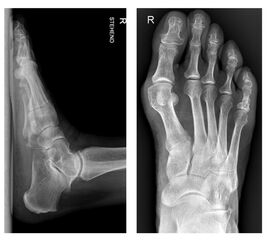

Die Akin-Osteotomie erfolgt in mindestens 50% begleitend zu metatarsalen Osteotomien im Rahmen der Korrektur einer Hallux valgus Deformität 12. Diese gehören zu den am häufigsten durchgeführten orthopädischen Eingriffen. Eine präzise Planung der notwendigen Korrektur unter Berücksichtigung aller Komponenten ist daher unabkömmlich. Dabei sollte eine Valgus-Deformität der Grundphalanx mitbehandelt werden, da diese die Entwicklung eines Rezidivs begünstigt. Die valgische Deformität der Grundphalanx mit veränderten Gelenksflächenwinkeln wird als Hallux valgus interphalangeus bezeichnet (Abb. 1). Dabei können verschiedene Winkel zur Definition der Fehlstellung angegeben werden (Abb. 2) 34. Bei der Beurteilung des Hallux valgus interphalangeus im Rahmen einer Hallux valgus Deformität ist zu beachten, daß häufig eine Hyperpronation der Grundphalanx besteht. Durch diese Malrotation werden die eigentlichen pathoanatomischen Winkel "verprojiziert". Am Röntgenbild erscheinen diese projizierten kleiner als die reellen Winkel. Somit sollte intraoperativ nach einer metatarsalen Osteotomie überprüft werden, ob eine Restfehlstellung im Sinne eines Hallus valgus interphalangeus besteht, da das präoperative Röntgenbild die Fehlstellung nicht immer exakt abbildet.

• Hallux valgus interphalangeus (Abb.1, Abb.2, Abb.3).

• Röntgenaufnahme des Fußes (unter Belastung) in dorsoplantarem und seitlichen Strahlengang (Abb. 3) und präoperative Fotodokumentation.

• Beurteilung des proximalen Gelenkflächenwinkels der Grundphalanx (Proximal Phalangeal Articular Angle, PPAA) des Hallux valgus interphalangeuswinkels (Hallux interphalangeus Angle, HIA) sowie des proximalen zum distalen Gelenksflächenwinkel (Proximal to Distal Phalangeal Articular Angle, PDPAA) 6789 (Abb. 2).

• Bei Hallux valgus Problematik: Bestimmung des ersten Intermetatarsalwinkels (IMA), des Hallux valgus Winkels (HVA), des distalen metatarsalen Gelenskflächenwinkels (DMAA) 68.